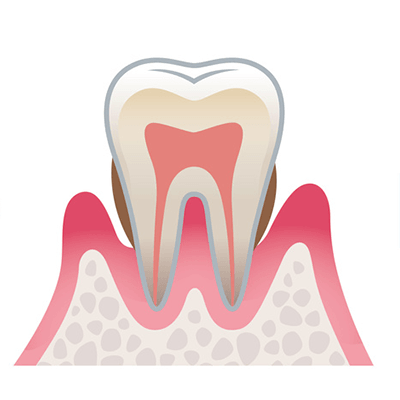

2.中等度歯周病

炎症が進行し、歯を支える顎の骨にまで歯周病菌が及びます。

歯周ポケットはさらに深くなり、歯の揺れを感じ始めます。

2.中等度歯周病

炎症が進行し、歯を支える顎の骨にまで歯周病菌が及びます。

歯周ポケットはさらに深くなり、歯の揺れを感じ始めます。